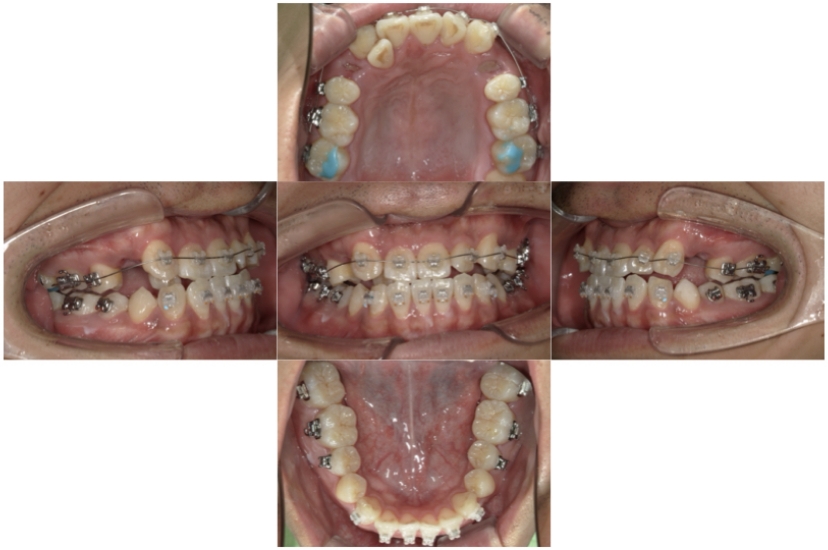

BEFORE

治療経過

上下顎叢生(上下の前歯のガタガタ)のケースです。

装置はラビアル(上下表側)で、上下顎の小臼歯を4本抜歯を行っています。抜歯したスペースを使って、上下の前歯の後方移動と叢生(ガタガタ)の改善を行っています。

主訴 歯並びが悪く、舌を噛んでしまうのを治したい。

年齢・性別 27歳 男性

お住まいの地域 東京都大田区

治療方針 抜歯スペースを利用して上下前歯の叢生(ガタガタ)の改善

抜歯部位 上下顎左右第一小臼歯

使用装置 ラビアル(上下表側)、顎間ゴム

治療期間 3年1か月

治療回数 30回